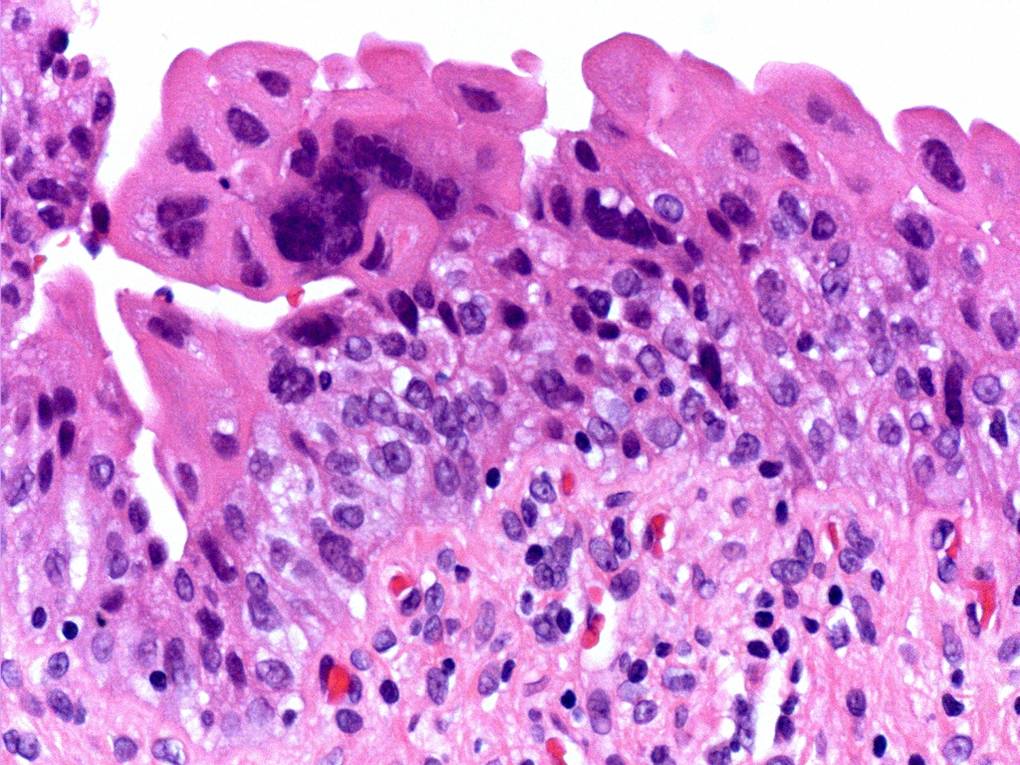

Consensus grade: Reactive atypia

Case description (by case creator):

The main change here is ‘degenerative’ nuclear atypia in a rather unusually prominent umbrella cell layer. The underlying urothelium shows mild reactive changes in places with some chronic inflammation in the lamina propria.